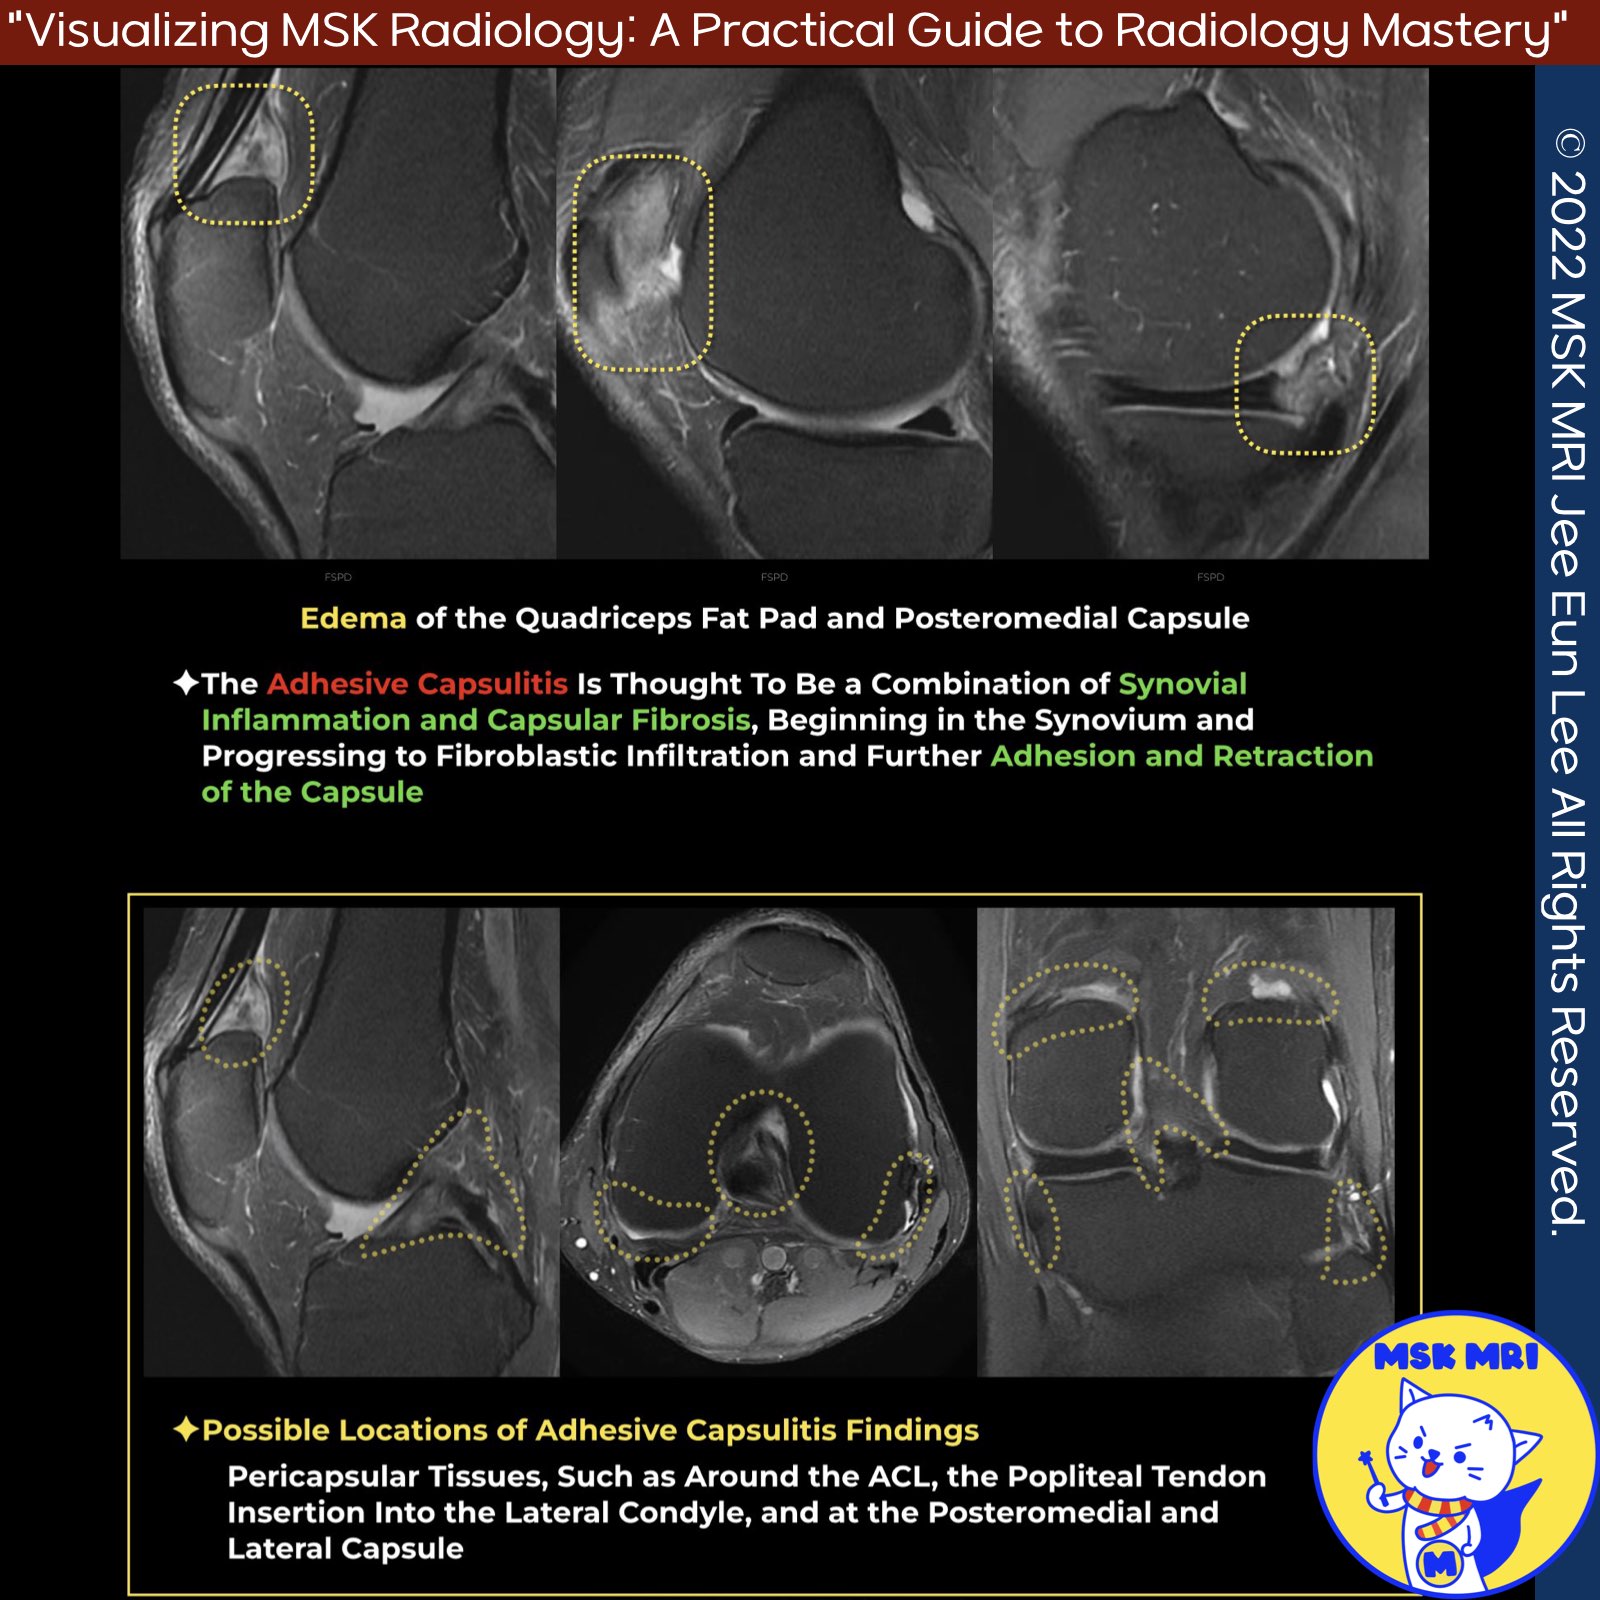

📌Adhesive Capsulitis

- Adhesive capsulitis (AC) is a condition characterized by synovial inflammation and capsular fibrosis, leading to fibroblastic infiltration, adhesion, and retraction of the capsule.

✅ Imaging Findings:

- Imaging findings in affected joints include high signal intensity on fluid-sensitive images and contrast enhancement of the pericapsular tissues, such as around the anterior cruciate ligament (ACL), popliteal tendon insertion, and the posteromedial and lateral capsule in the knee.

- De Abreu et al. reported a case of knee pain with high T2 signal diffusely along the ACL, suprapatellar fat pad, and posteromedial capsule. Fluorodeoxyglucose positron emission tomography/computed tomography revealed extensive enhancement of the same structures, as well as the posterior cruciate ligament (PCL), popliteus insertion, posterior capsule, and semimembranosus (SM) insertion.